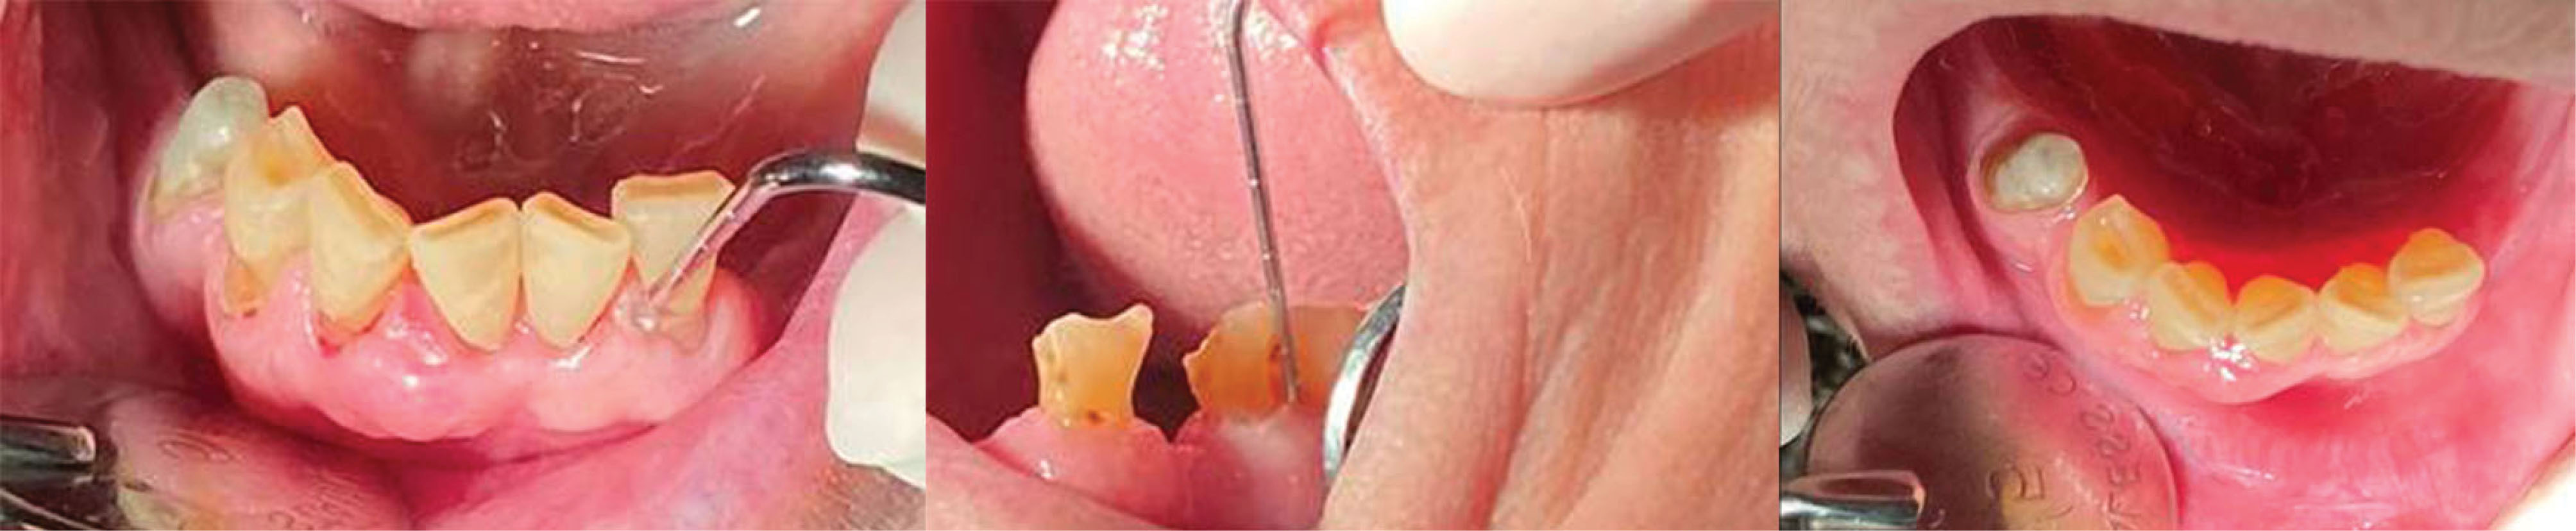

japid-13-22-g004

Figure 4. Photo of a 92-year-old patient in the group of patients for cross-sectional data, showing the evaluation of the bleeding index after probing and measuring attachment loss. We also draw attention to the presence of pronounced gingival recessions.